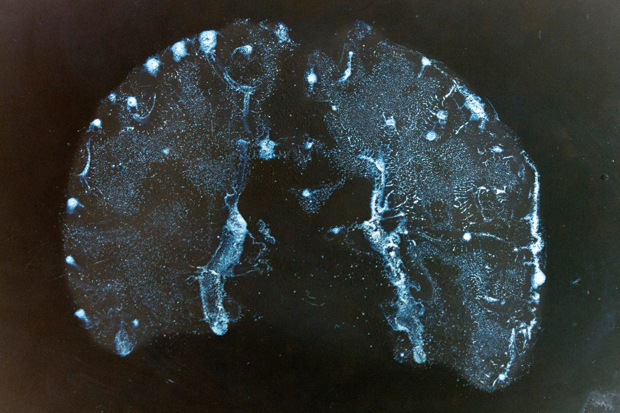

The curators have placed the centrepiece of their latest exhibition, Susan Aldworth’s lithographs, including ‘Passing Thoughts 13’ (above), on the wall of the partition facing the walkway. Whether or not this decision was intentional or forced, it was inspired. The blurb says that the lithographs ‘reflect on the general condition of schizophrenia’, and it’s not lying. To contemplate these images, while purposeful strangers stride about you to a disjointed background soundtrack of clunking doors and invisible voices, is deeply unsettling. The Blyth Gallery would make a poor show of John Constable; but it’s perfect for Aldworth’s meditations on consciousness, psychosis and the physical brain. Until 1 May.